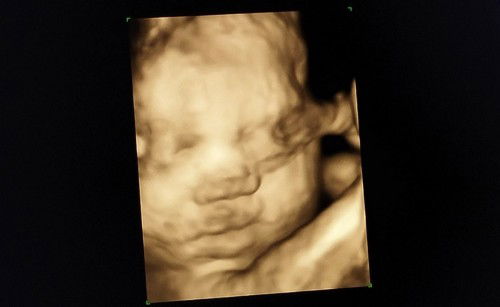

Super happy, idk sino kamukha di talaga ko marunong tumingin kapag baby pa 😅 Madami nag sasabi ako daw madami din nag sasabi yung hubby ko daw. Hahahaha. Kahit sobrang likot st kulit mo daw sabi ni doc, thank you pa rin po anak kasi nagpakita kapa rin saamin ni papa mo. Sobrang love ka namin at excited na kaming makasama ka ❣️#Happy_Mommy#firstbaby